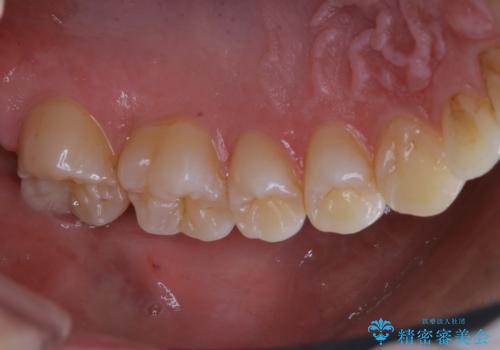

3カ月に1度のPMTCでオーラルケア

- 3カ月ごとに定期的にメンテナンスにいらしている方です。PMTC30分コースを行いました。

PMTC(保険外治療)は、毎日の歯磨きで落としきれない汚れや、タバコのヤニなどの着色も除去します。目には見えない歯と歯の間・歯肉の境目などに残っているプラーク(歯垢)もしっかり取り除きます。